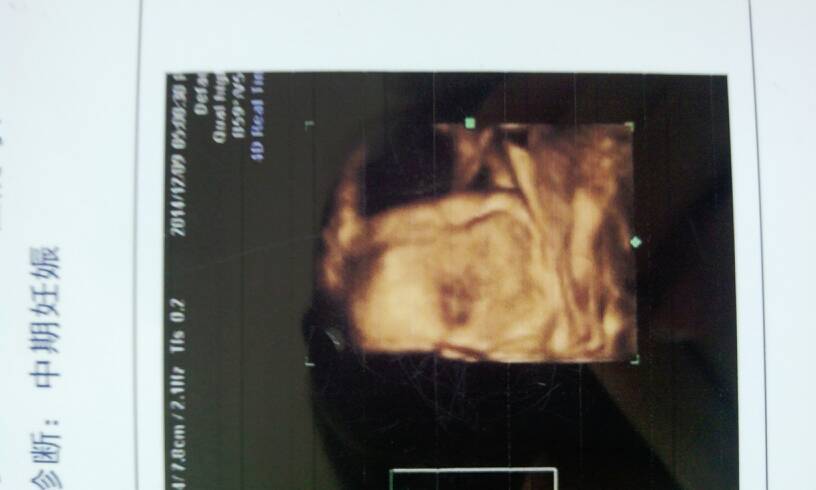

今天刚做的四维,亲们能看出来眼睛鼻子嘴巴吗?我怎么看不出来啊? 今天刚做的四维,亲们能看出来眼睛鼻子嘴巴吗?我怎么看不出来啊? 点击展开 89...8@qq.com 2014-12-09 13:24 为您推荐: 其他回答 超声毕竟和照片不一样,多少他还是通过?后期的重建来看的,主要是来,看他是否有畸形 最优秀医生 2014-12-10 12:42 拍的不好!看不清 150*****298 2014-12-09 13:39 四维怎么这么糊啊 150*****753_J1uB 2014-12-09 13:33 看不清楚哦。 堇色安年〤谁许我一世荒芜_DQa7 2014-12-09 13:32 我也没看懂。。。 伴我暖ヾ 2014-12-09 13:31 加载更多 相关问题 做四维彩超能看清宝宝的眼睛,鼻子吗? 4个月宝宝放婴儿车里推着突然眼睛、鼻子、嘴巴流了很多奶 两个月宝宝眼睛鼻子嘴巴都热而且体温38度